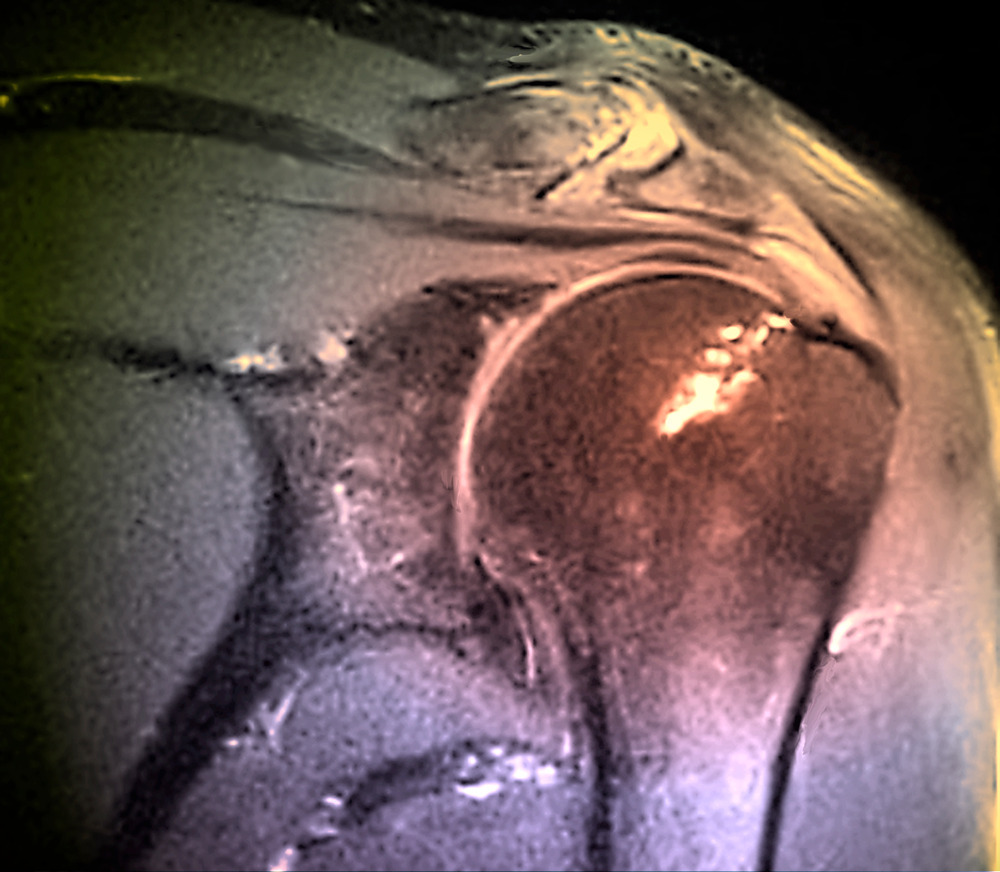

석회화건염

"잠자다 깰 만큼 어깨가 아프다면

석회화건염을 의심해보아야 합니다."

힘줄에 칼슘이 쌓이면서 염증과 극심한 통증을

유발하는 어깨 질환입니다.